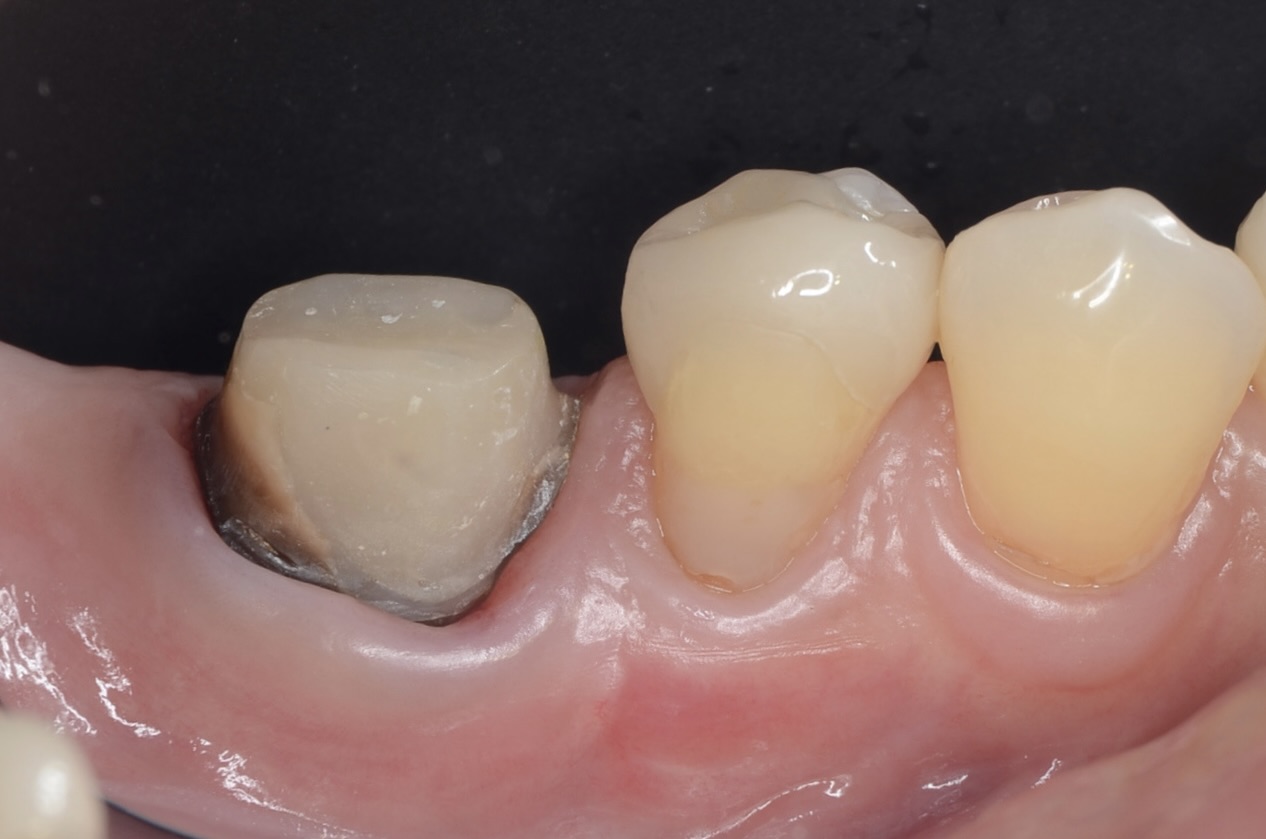

50代 虫歯がひどい歯を歯周外科とジルコニアクラウンで治す

Before

保険治療のクラウンで

クラウン除去

レジンコア除去後

歯頸部の歯肉縁下にまで虫歯が広がっていました。 通常であれば、抜歯になります。 -